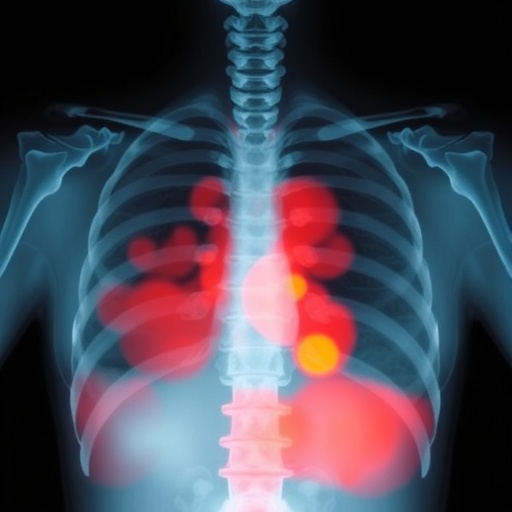

In a groundbreaking study published in Archives of Osteoporosis, researchers have harnessed the revolutionary power of artificial intelligence to enhance the screening process for low bone mass conditions using chest X-rays. This novel approach utilizes knowledge distillation, a method within deep learning that optimizes the performance of AI models, to identify patients at risk of osteoporosis. The implications of this research transcend traditional methods of bone density measurement, potentially reshaping the preventive landscape in osteoporosis management.

Within the study led by Park et al., the team devised an innovative framework that leverages existing chest X-ray images, commonly used for other diagnostic purposes, to evaluate bone mass. The ability to repurpose these images could lead to more efficient and widespread screening, especially in populations with limited access to specialized bone density testing. This not only can identify patients earlier but may also facilitate timely interventions that can significantly alter disease outcomes.